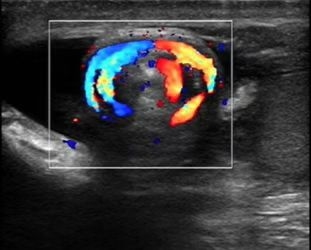

1.直接征象:扭转的精索,“漩涡征”

2.间接征象:因精索扭转缩短而睾丸位置抬高,睾丸长轴由正常的斜位扭转为横位,睾丸回声不均。彩色多普勒:双侧对比,早期患侧血流信号明显减少,晚期血流信号消失。